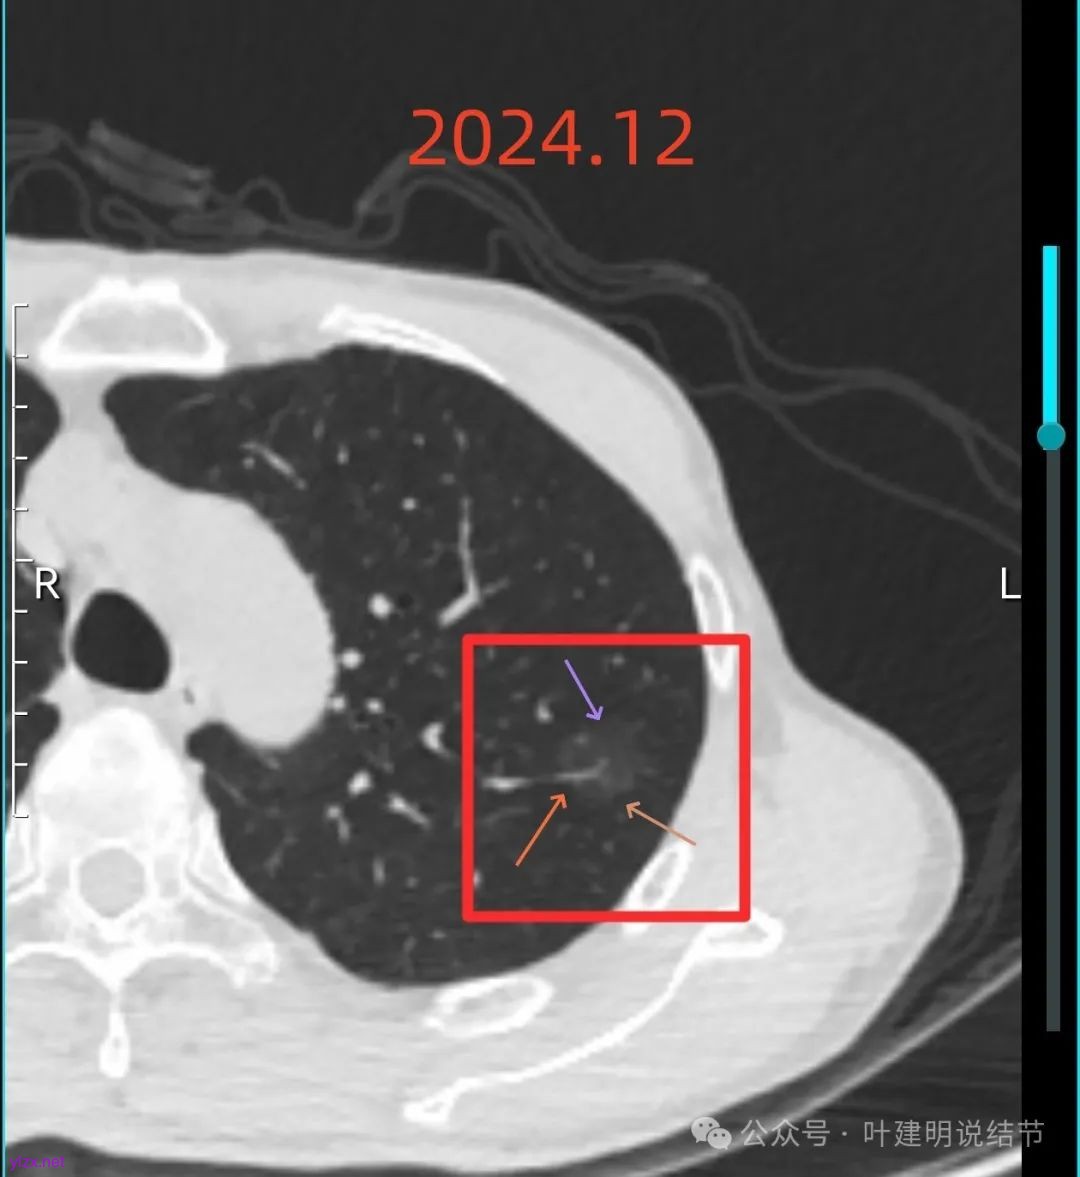

左上病灶血管进入了病灶且有异常增粗,边缘有淡的细毛刺的样子。

灶内血管明显,管壁略毛糙,有异常增粗,红色箭头处有点状高密度,边缘有毛刺征。

灶内出现了明显的实性成分,整体轮廓较清。

除了原血管进入外,另外角度也见到其他血管发出分支走向病灶,而且灶内密度不均,实性成分明显。